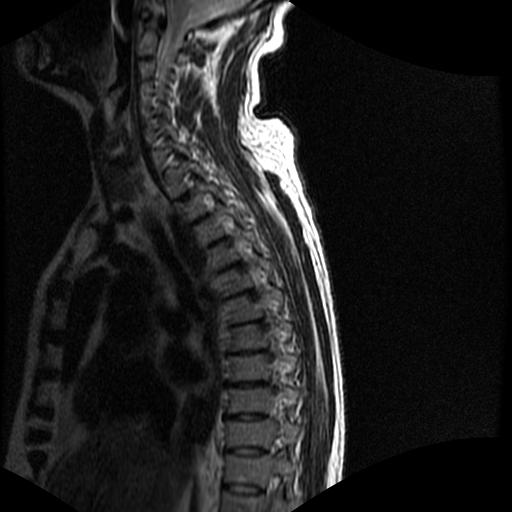

标题: MRI0985:胸椎.68岁男性,胸部疼痛,

68岁男性,胸部疼痛,不适。

t7椎体前1/3信号略减低,椎体上下面凹陷,相应脊髓几周边软组织信号未见改变。考虑:椎体退变。

胸7椎体楔状变形及信号异常,附件未见明显异常信号.椎间隙正常.未见软组织块影.考虑骨质疏松所致压缩性骨折可能大.

胸7椎体楔状变形及信号异常[t1t2 均为低信号],附件未见明显异常信号.椎间隙正常.未见软组织块影.考虑陈旧性压缩性骨折伴退变。